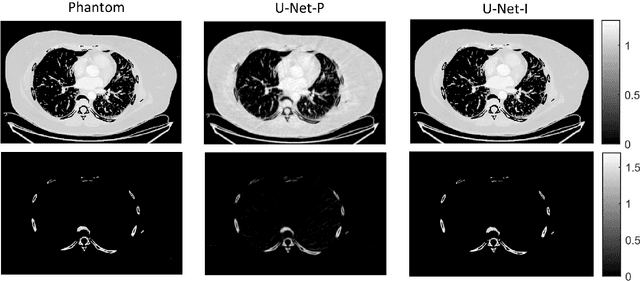

Abstract:Spectral computed tomography (CT) has recently emerged as an advanced version of medical CT and significantly improves conventional (single-energy) CT. Spectral CT has two main forms: dual-energy computed tomography (DECT) and photon-counting computed tomography (PCCT), which offer image improvement, material decomposition, and feature quantification relative to conventional CT. However, the inherent challenges of spectral CT, evidenced by data and image artifacts, remain a bottleneck for clinical applications. To address these problems, machine learning techniques have been widely applied to spectral CT. In this review, we present the state-of-the-art data-driven techniques for spectral CT.